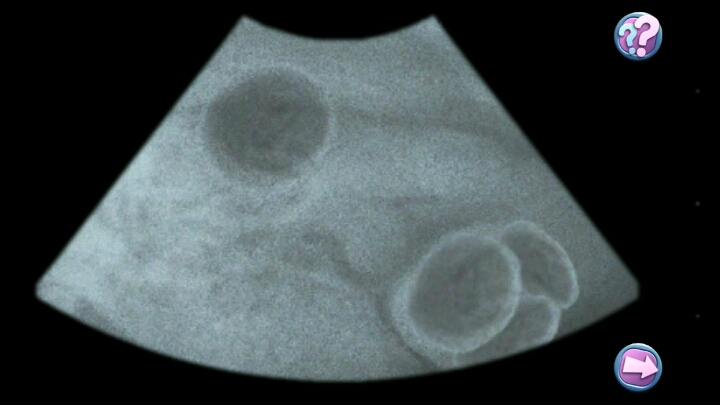

这个游戏最厉害的地方在于治疗动物的过程,简直真实到不行。

清除皮肤上的跳蚤和异物,检查耳朵,用听诊器检查内脏,剪爪子,点刺实验,血液检查,接种疫苗,检查发烧,清洁牙齿,照X光,超声检查。

每一项都有专门需要的器材,非常专业。